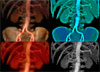

- Спиральная компьютерная томография с контрастированием.

Врачи любого профиля в практической работе могут встретиться со случаями аневризмы аорты и ее...